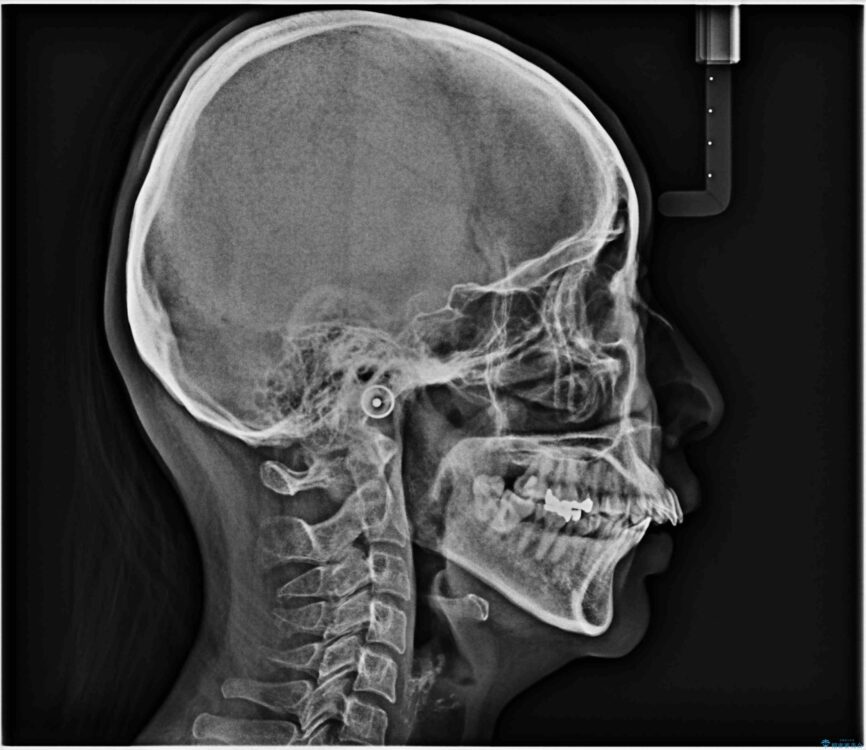

治療前

• 上顎前歯の突出を軽減 インビザラインによる抜歯矯正 治療前画像